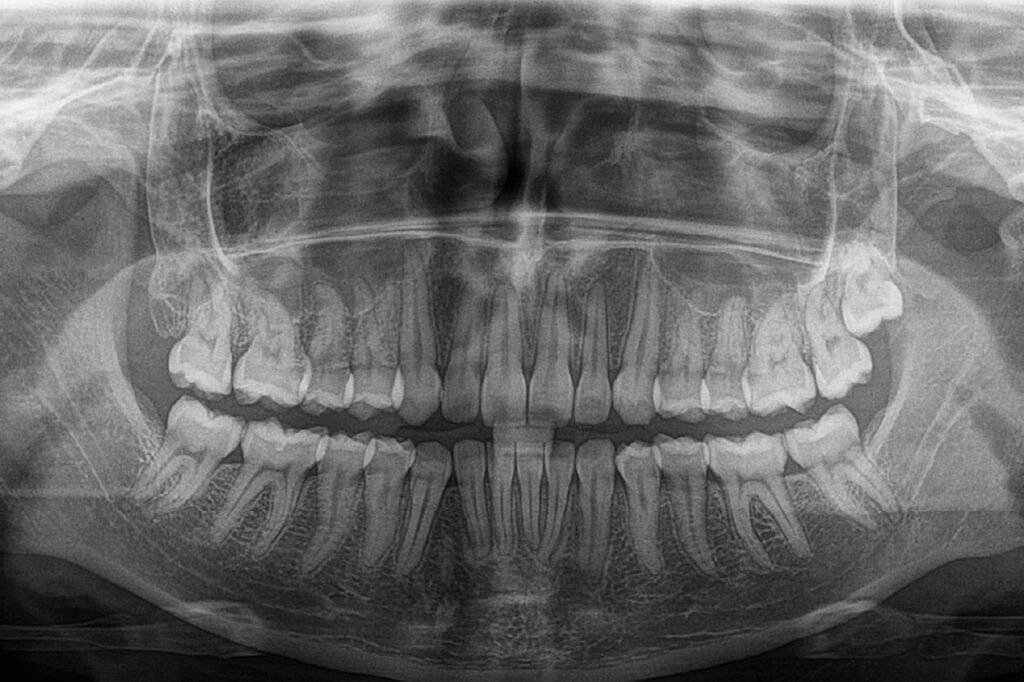

Radiografías Extraorales

- Rx Panorámica estándar